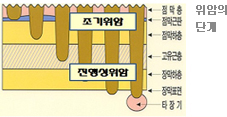

| 18 | 위내시경 | 검진동 3층 | 약 10분 | 식도질환, 위염, 위궤양, 십이지장 궤양, 위암, 헬리코박터파이로리균검사 등 |       |

| 19 | 대장내시경 | 검진동 3층 | 약 20~30분 | 대장의 염증, 궤양,

용종, 암

(특히 조기암 발견) 등 |